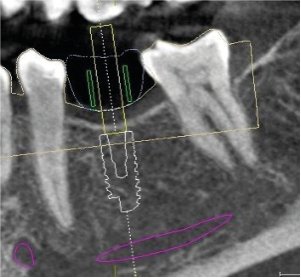

se realiza planeación quirúrgica computarizada, confección de guía de fresado y de provisionales acrílicos.

Zona postero superior derecha para aprovechamiento del hueso disponible y evitar elevacion de seno maxilar.